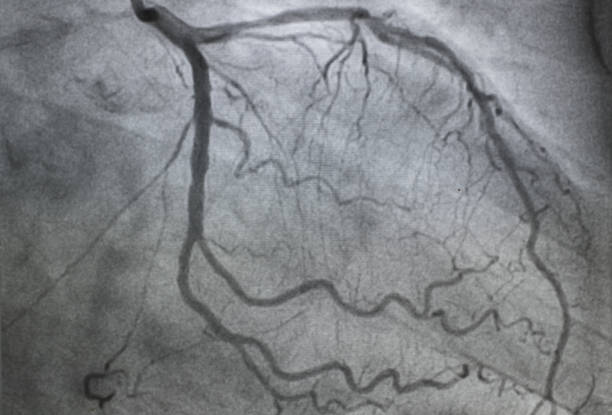

Nasci com um suposto sopro que me mascarou por completo a minha deficiência – eu afinal tinha era um coração completamente estragado e que se foi continuando a estragar até ter que ser mudado por outro.

Mas essa mudança não fez de mim uma pessoa nova e sem problemas: o coração estragado fez alterações ao meu organismo, e na verdade, o que eu precisava era que me trocassem todos os órgãos e só me mantivessem o cérebro (isto para que eu fosse eu mesmo, porque agarrar nisto tudo e deitar fora talvez fosse uma opção). Mas o esforço dos médicos em me manter viva era impressionante!

Este blogue é sobre as dificuldades de se viver com uma incapacidade deste género (insuficiência cardíaca, que se estende para o corpo todo), e como essa deficiência me afecta a mim e afecta o mundo à minha volta. E como o mundo em que vivemos me afecta, tendo em conta esta deficiência.